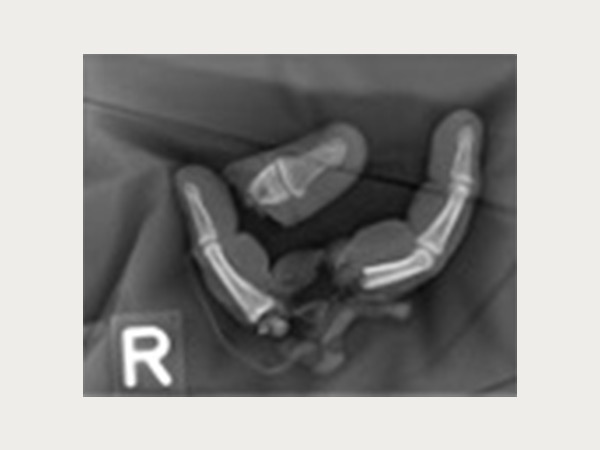

Wenn es zu einer komplexen Handverletzung kommen sollte, sind Sie an unserem standortübergreifenden Zentrum im Notfall rund um die Uhr bestens aufgehoben. Arbeits- und Wegeunfälle (Berufsgenossenschaft) werden schwerpunktmäßig behandelt. Dank der Zulassung als Schwerstverletzungsartenverfahren (SAV) Hand Trauma Zentrum durch die DGUV konnten wir bestmögliche Bedingungen zur chirurgischen Versorgung von schwersten Handverletzungen inklusive Fingeramputationen schaffen. Ein handchirurgisches Replantationsteam steht rund um die Uhr zur Verfügung.